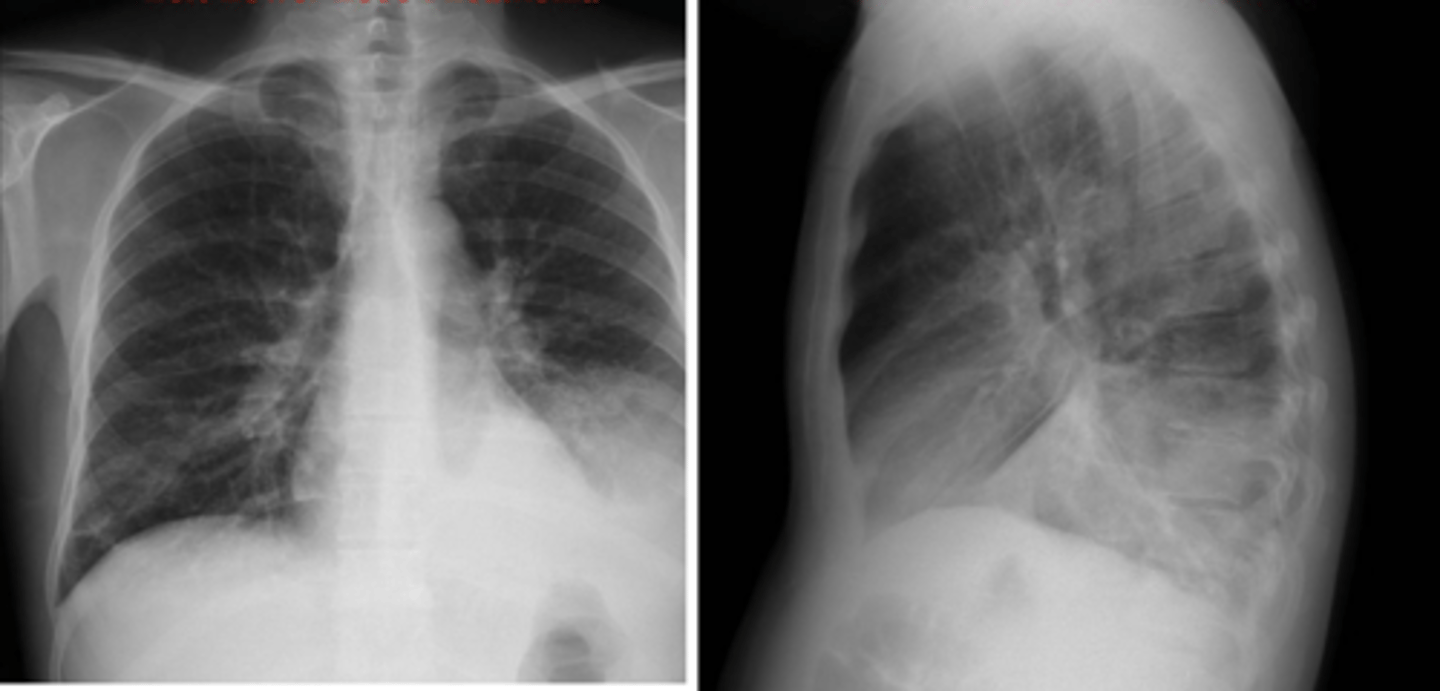

•Routine CXRs include PA and lateral views with the patient in the upright position.

⚬AP and supine (portable) films make the heart appear enlarged and the lungs hypoinflated.

⚬A lateral decubitus film can aid in identifying a pleural effusion.

⚬Lordotic films are used to view the apices of the lungs

⚬Expiratory view may be helpful for pneumothorax